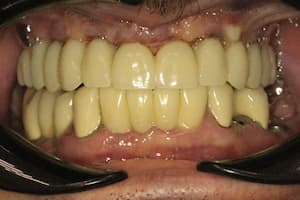

Альтернативный вариант несъемного протезирования. Полная адентия (отсутствие) зубов на верхней челюсти. Применения технологии all on 6. Имплантация 6 зубов системой Neodent на верхней челюсти. Протезирование зубов коронками Telio Cad армированными титановой балкой.

После

Удаление семи зубов на верхней челюсти. Одномоментная имплантация системой Neodent 6 зубов, предназначенная для немедленной нагрузки (изготовление временных коронок в день имплантации). В день имплантации сняли оттиски для временного протезирования Telio Cad. Конструкция была установлена через 2 недели после имплантации.